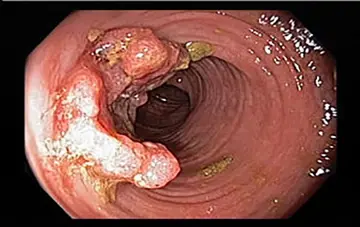

روش ریشه‌کنی هلیکوباکتر پیلوری

شماره ۱۱۱۹